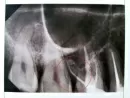

По данным приложенного снимка однозначно сложно судить, так как контрастируется не четко, то похоже на атрофию костной ткани. Но это может быть артефакт снимка.

Следует сделать трехмерный снимок, для полноценной оценки состояния тканей.